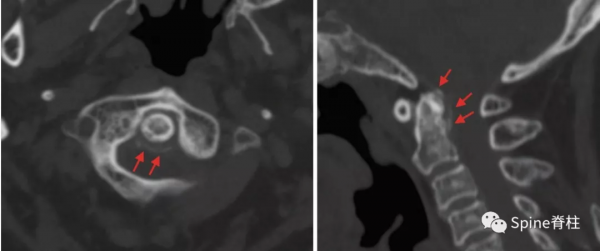

圖:C2-3兒童頸椎間盤鈣化合並後縱韌帶骨化

雖然本病可以發生在從新生兒到青春期, 但其發病高峰為6~10歲,男性多於女性,發病部位以頸椎間盤最為多見,胸椎次之,腰椎最少,頸椎中以C6-7和C3-4節段最為常見。一般為單一節段的椎間盤鈣化,少數病例也可有兩個部位的椎間盤鈣化,部分病例可伴有後縱韌帶骨化。另外,部分病例可出現神經刺激症狀,且在影像檢查中不僅可以看到椎間盤異常徵象,還可顯示腫塊侵入椎管,甚至壓迫脊髓,特別是合併後縱韌帶骨化的病例,椎管侵佔率往往大於50%。

圖:患者8歲,女孩,因嚴重頸部疼痛、活動受限伴左上肢無力、麻木不適2天就診。既往有鎖骨骨折、額部軟組織挫傷病史。查體:頸椎活動受限,左上肢肌力正常,但感覺減退。白細胞、血沉、CRP升高。頸椎側位片和CT平掃提示C6-7椎間盤鈣化(粗箭頭)和後縱韌帶骨化(細箭頭),頸椎MRI提示C6-7水平脊髓明顯受壓。給予頸椎制動、枕頜帶2.5kg頸椎牽引2周。隨後,頸託固定1個月。2年後隨訪複查頸椎CT如下圖,同時上述症狀完全緩解。

圖:2年後複查CT示C6-7鈣化的椎間盤和後縱韌帶骨化都消失了